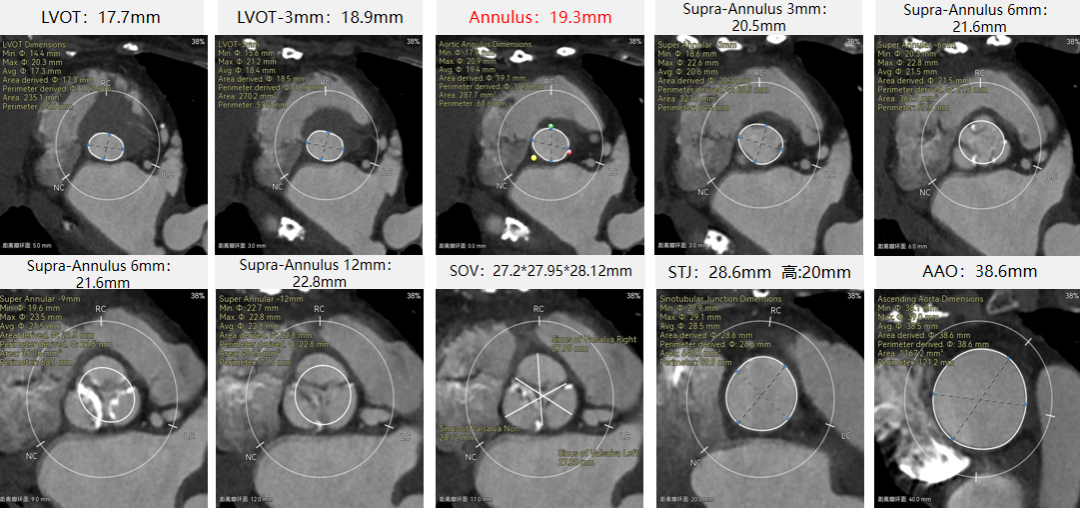

刘煜昊教授 阜外华中心血管病医院(点击查看专家详细简历) 首瓣选耐久,干瓣护航全生命周期管理 2025年ESC专家共识里指出:“推荐第一个瓣膜要选经证实具有长期耐用性的外科瓣膜与经导管瓣膜,以降低再次介入治疗的可能性 ,对于瓣环较小、根据预测有效瓣口面积(EOA)评估存在严重 PPM 风险的患者,可采用主动脉根部扩大术联合 SAVR,或植入环上瓣,对于小瓣环患者自展瓣拥有比较好的血流动力学优势”。 每一次术前评估,都是我们与患者携手面对未知的起点。我们始终以患者全生命周期获益为核心,在瓣膜选择与术式规划中,不只着眼于当下解剖适配,综合评估解剖条件、预期寿命与生活质量。从年轻患者到高龄人群,瓣膜耐久性与血流动力学稳定性始终是决策核心! 陈同峰教授 阜外华中心血管病医院(点击查看专家详细简历) 医学的进步正不断拓宽生命的边界,每一次术前评估都是对生命尊严的深度凝视,技术与人文的交融,让风险不再仅是数字的堆叠,而是成为医者与患者共同面对未知的勇气见证。术中瓣膜释放结束,到了导管测压的时候,我惊喜:瓣膜不错啊,压差为0,这不仅仅得益于瓣膜形态的设计,更是环上瓣及瓣叶材质优质的体现,感受到了 Prostyle A瓣膜在血流动力学上的卓越表现,其采用的抗钙化处理技术有效延长了瓣膜的耐久性,为患者长期生存提供了更可靠的保障。 患者病史 主诉:心慌半月; 门急诊诊断:心悸,冠状动脉粥样硬化性心脏病,心脏瓣膜病,主动脉瓣狭窄,高血压,甲状腺术后; 现病史:半月前无明显诱因出现心慌,呈间断性,伴心悸、出汗,伴头晕,无咳嗽、咳痰,无恶心、呕吐,无双下肢水肿,无放射痛及意识障碍,休息约几分钟后可自行缓解,症状反复发作,遂来我院就诊。 术前超声提示:室间隔增厚;主动脉瓣退行性变并重度狭窄;升主动脉明显增宽;室间隔增厚。 术前CT 三叶瓣,轻度钙化集中在无窦和左窦瓣叶边缘,主动脉根部直径19.3mm,LVOT直径17.7mm,LVOT向下收窄; 窦部正常,VTC空间足够,冠脉风险低; 左室腔小,收缩末径20-25mm,“自杀左室”,循环崩溃风险高;主动脉瓣环水平夹角71.1°,横位心,过弓和跨瓣存在一定困难,备snare。 外周双侧入路内径可,双侧入路能够支持20F大鞘通过,右股低分叉。 手术策略 推荐右侧股动脉为主入路,左侧为辅助入路,右股分叉上方1cm穿刺;推荐选择AV23瓣膜,18mm球囊预扩,左右重叠位:LAO 7° CAU 35°;左冠切线位:LAO 27° CRA 16°;右窦居中位:LAO 18° CAU 9°;备Snare,建议ECMO/CPB湿备,术前术中积极补液,警惕循环崩溃风险。 手术过程 在右股动脉穿刺建立通路后,顺利送入大鞘,经食道超声及血管造影确认路径稳定。18mm球囊预扩过程中,患者血压一度下降,迅速完成扩张并立即植入AV23 ProStyle A®瓣膜。瓣膜精准释放于目标位置,超声显示无明显反流及瓣周漏,血流动力学即刻改善。 主动脉根部造影 18mm球囊预扩少量反流 输送系统柔顺跨瓣 精准定位 平稳释放 80%工作位观索位置合适 释放后导管测压,压差由术前53mmHg降为0mmHg 最终造影瓣膜位置形态良好,冠脉灌注良好,无明显瓣周漏 ProStyle A®预装干瓣——助力临床最优化解决方案: 轻松过弓,精准可控:该病例为横位心,在未使用snare的情况下,过弓和跨瓣柔顺,较细的尺寸+柔顺的输送系统通过性能得到了很好的验证; 平衡的收腰设计:该病例瓣环较小且左室腔小,AV23瓣膜的平衡收腰设计既确保了锚定安全性,又保证了EOA,有效降低了循环崩溃风险,而术后0mmHg的压差的表现更加证明了优秀的血流动力学,提高了瓣膜的耐久性; 预装干瓣 便捷顺安:金仕生物专利抗钙化技术运用纳米技术去除组织内的细胞碎片和磷脂,封闭游离醛基,从根本上阻断了瓣膜钙化的多项因素,显著提升了瓣膜的耐久性;同时,相比较传统戊二醛保存方式,干式存储最大限度的保留心包的亲水亲油平衡,还原组织天然曲柔性,进一步保障了瓣叶开合,保证长期耐久性。 专家简介 王小虎 阜外华中心血管病医院(点击查看专家详细简历) 陈冲 阜外华中心血管病医院(点击查看专家详细简历) 赵一品 阜外华中心血管病医院(点击查看专家详细简历)